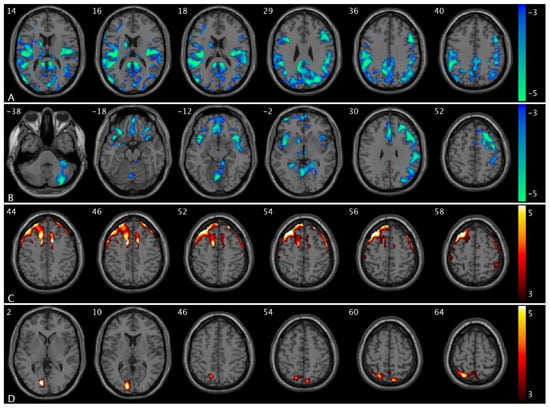

We observed significant group and urge interaction effects for CBF and PCC FC (Figure 1). Compared to healthy controls, OAB participants demonstrated significant decreases in ΔCBF (from low to high urge) in the medial prefrontal region, specifically in the superior frontal and superior medial frontal areas (Figure 1A). There were significant increases in ΔCBF (from low to high urge state) in the cuneus, supramarginal extending to inferior parietal, middle, and superior temporal regions (Figure 1B). There were significant decreases in ΔPCC FC (from low to high urge) in the insula, putamen, and pallidum regions (Figure 1C). A summary of the clusters’ statistics is reported in Table S1.

Figure 1. Statistical maps overlaid on T1-weighted images showing group and urge interaction effects. (A) Decreases in ΔCBF (from low- to high-urge state) in the superior frontal and superior medial frontal regions; (B) increases in ΔCBF in the cuneus, supramarginal extending to inferior parietal, middle, and superior temporal regions; (C) decreases in ΔPCC FC in the insula, putamen, and pallidum regions in OAB participants compared to healthy controls. The numbers in the top left corner of the MRI images indicate the z-coordinate (in mm) in the MNI space. The color bars represent t-values.